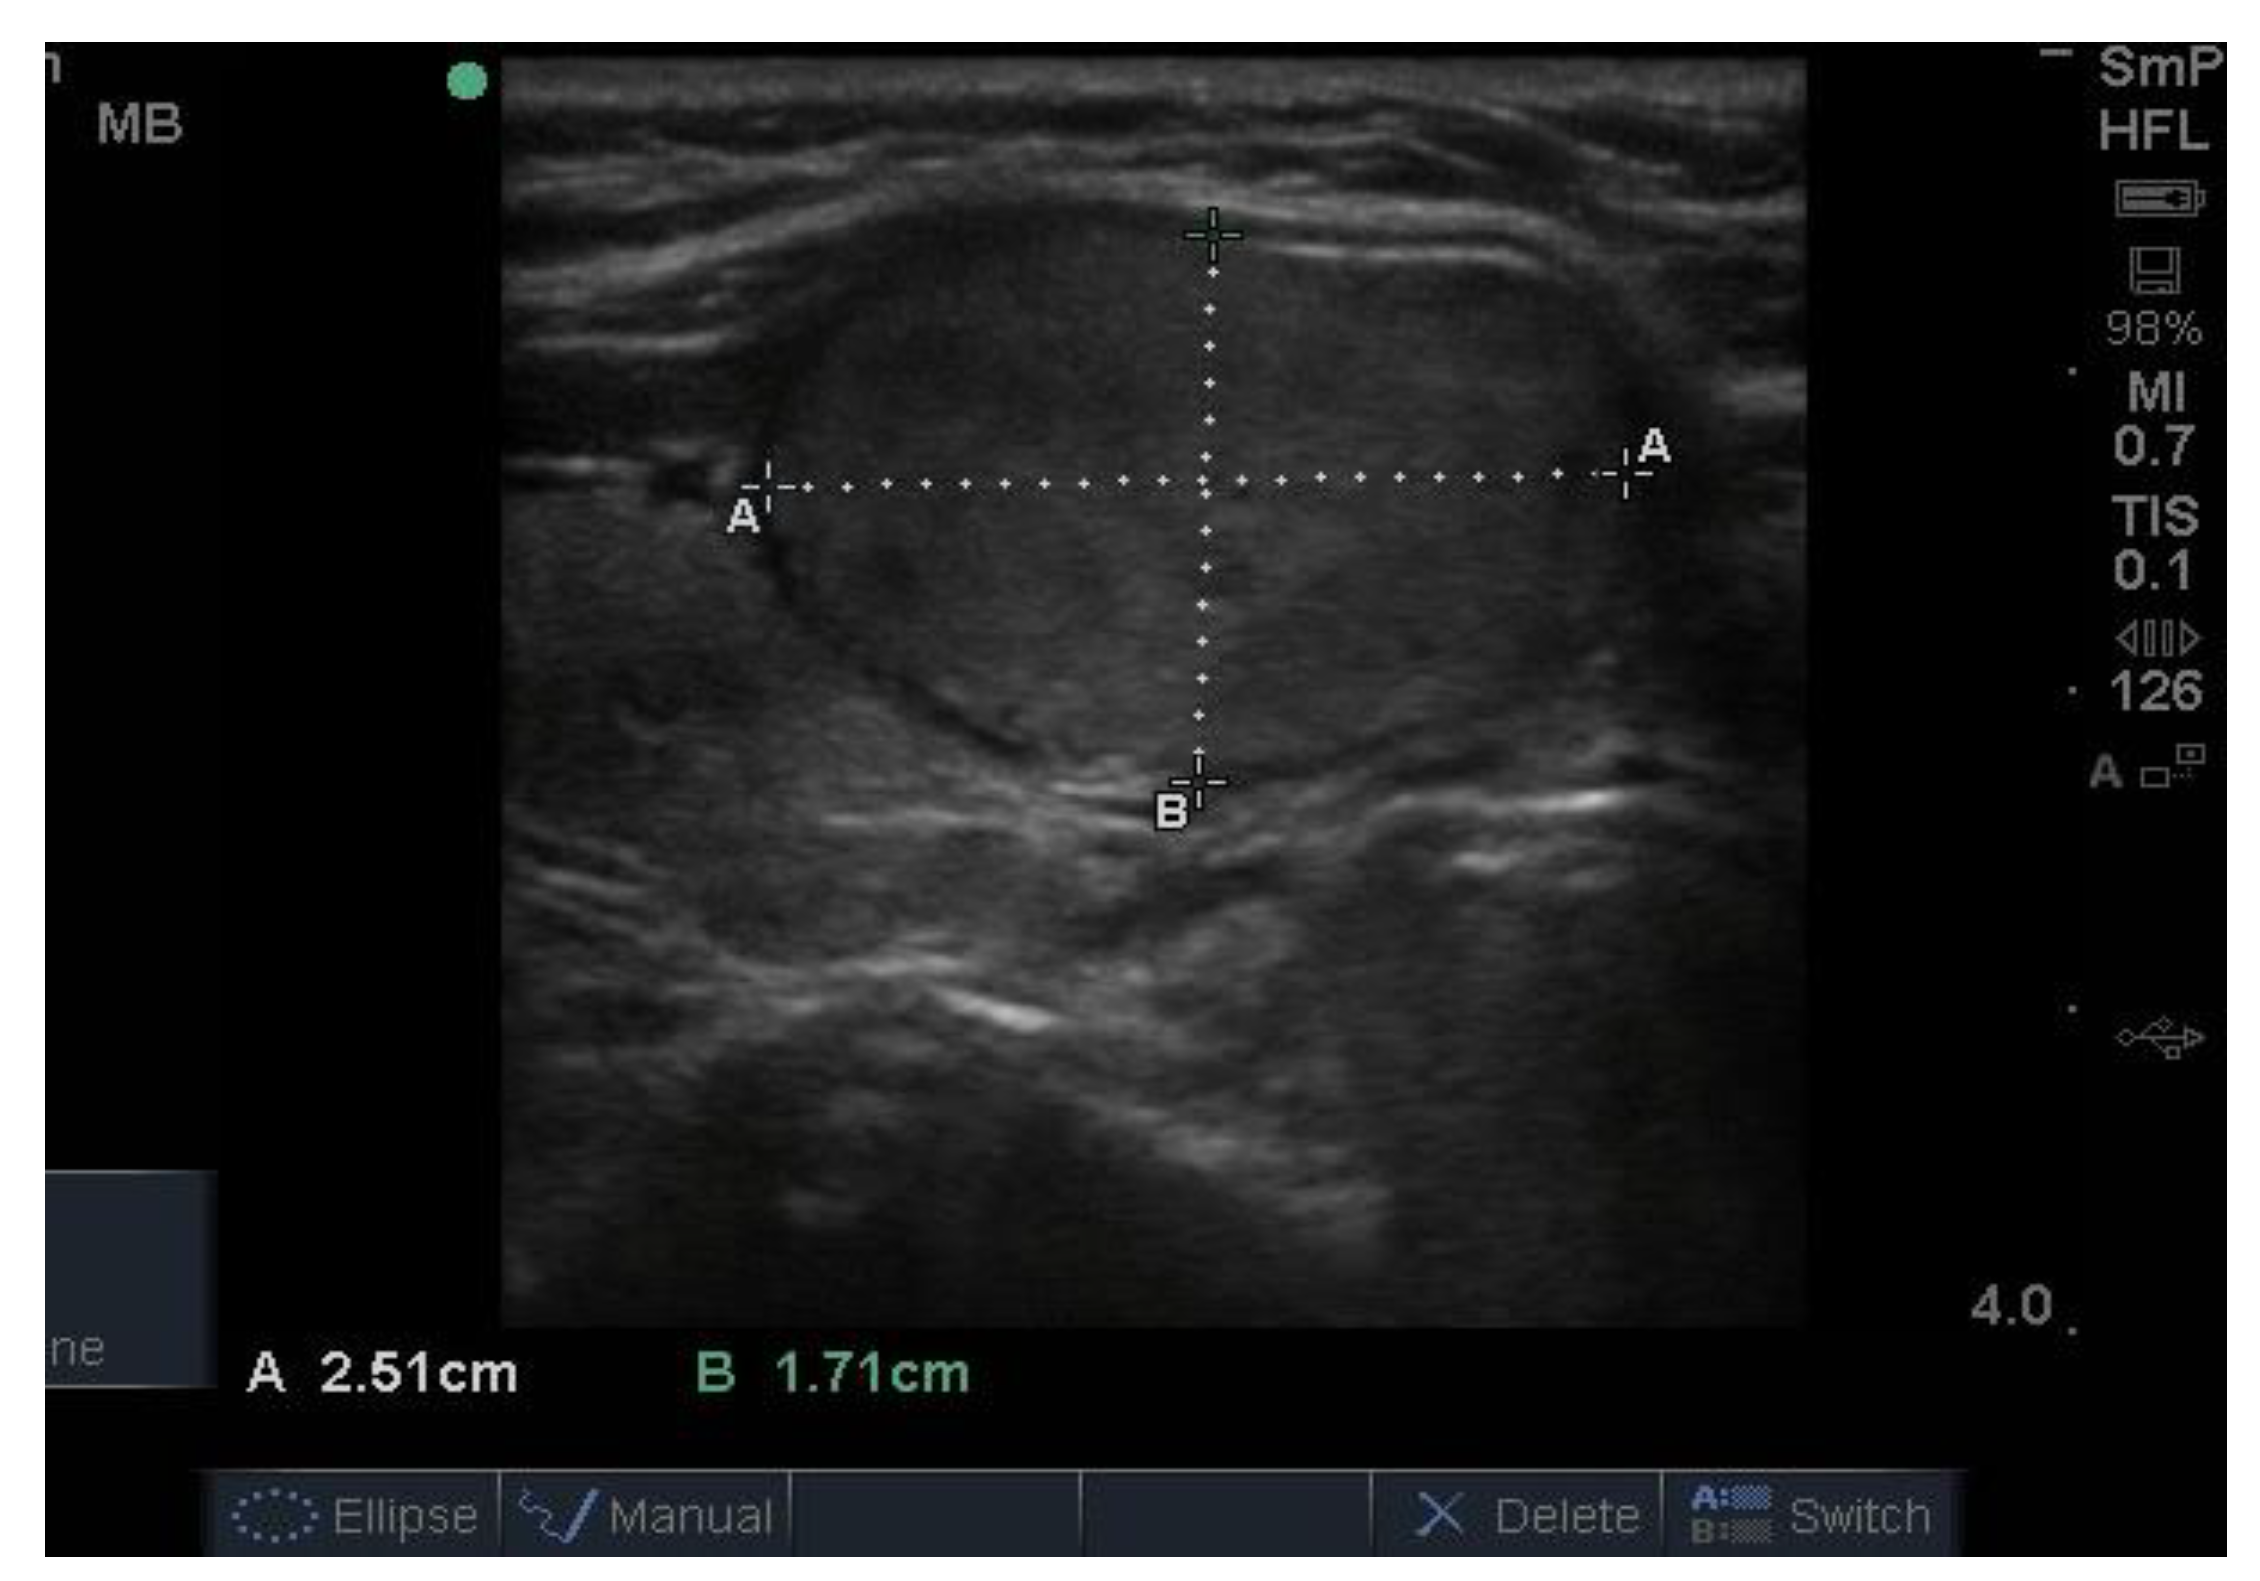

Follicular nodules are much less common than colloid nodules with a different appearance on ultrasound; they are more cellular, giving a solid appearance, with a whitish colour, i.e., less hypoechoic. They too have a sharp edge and halo and grow slowly over time [5]. The problem with these lesions is that FNAB is unable to differentiate between a benign follicular adenoma and follicular cancer, and if the latter is suspected, thyroid surgery is the final arbitrator. About 10% of benign thyroid nodules are follicular, and most of them end up being removed. Two examples of follicular nodules that were finally proven to be benign are shown in Figure 4. On follow-up ultrasound (US), 6–12 months later, repeat biopsy might be indicated if a nodule has grown by 20% or more in two or more dimensions; benign nodules also grow, but less quickly.

Figure 4. Two examples of follicular nodules that were shown at surgery to be benign. The nodules are roughly oval shaped, slightly hyper echoic and have sharp edges and, particularly, the bigger of the two, thick halos.